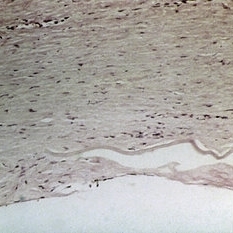

Slide 7-11

Feb 25 2019 by Lancaster Course in Ophthalmology

Noncaseating granuloma of the conjunctiva in a case of sarcoidosis.

Condition/keywords: conjunctiva, granuloma, sarcoidosis